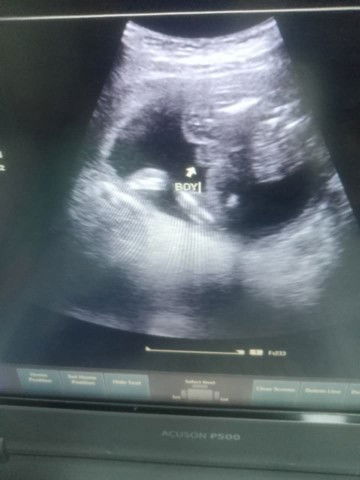

Nagpa ultra sound ako ng 5mos tummy ko confirm kaya na BOY po sya ?

ang sabi kasi ng ob ko saken na hindi pa sure yung gender pero nasabi nya saken nung inultrasound nyako na boy daw si lo tapos lately sinabi naman nya saken na need nyako iultrasound next week para ma sure nadaw gender confuse na tuloy ako puro panlalaki na kasi nabili kong gamit ni baby. baka may makatulong saken dito na matukoy ano talaga gender ni baby here is the picture below, Thankyou in advance đȘ»